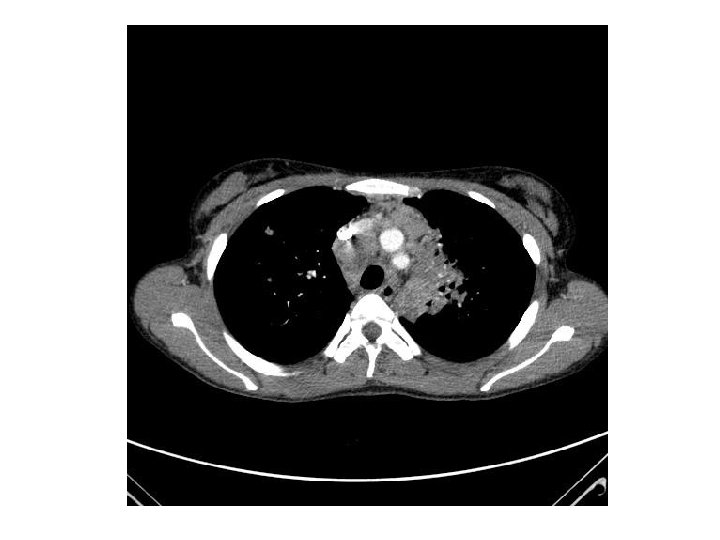

Evolution… Reste fébrile 39 -41°C 22/06: Fibroscopie bronchique 28/06: Antibiothérapie à large spectre 28/06 (J 17)Corticothérapie interrompue car absence d’amélioration • 15/07: Fibroscopie bronchique, TDM TAP • •

• 30/07: Reprise de la corticothérapie à 2 mg/kg/j pendant 21 j puis 1, 5 mg/kg/j • Vérification de la bonne observance thérapeutique • Antituberculeux par voie IV • Taux sériques antituberculeux normaux • Accalmie…avec une température qui diminue (38 -39°C) • Sortie le 20/08